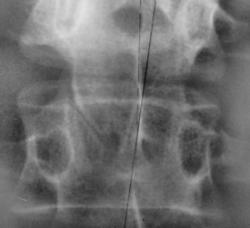

Иллюстрации 1, 2. Определяется деформация поясничного отдела позвоночника во фронтальной плоскости в виде правостороннего сколиоза. Произведена разметка – расчерчивание рентгенограммы по методу Фергюссона. Определяется ротация тел Л1, Л2, Л3, Л4 позвонков. При детальном изучении определяется вариант развития нижнего суставного отростка тела Л2 справа и верхнего суставного отростка Л3 справа в виде «скошенности».

Иллюстрация 3. Фрагмент с увеличением. Ранее, мы с таким вариантом развития не встречались.